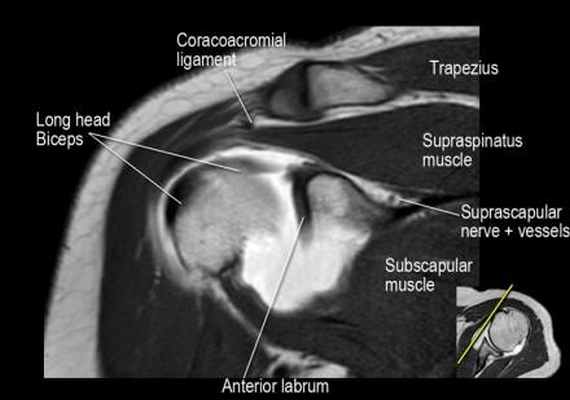

Нормальная корональная анатомия плечевого сустава и контрольный список

- изучите верхний комплекс двуглавой мышцы и суставной губы, поищите подгубный карман илм SLAP-повреждение

- поищите скопление жидкости в подакромиальной сумке и повреждение сухожидия надостной мышцы

- поищите частичный разрыв сухожилия надостной мышцы в месте его прикрепления в виде кольцевидного повышения сигнала

- изучите область прикрепления нижней плече-лопаточной связки. Изучите нижний комплекс суставной губы и связок. Поищите HAGL-повреждение (humeral avulsion of the glenohumeral ligament).